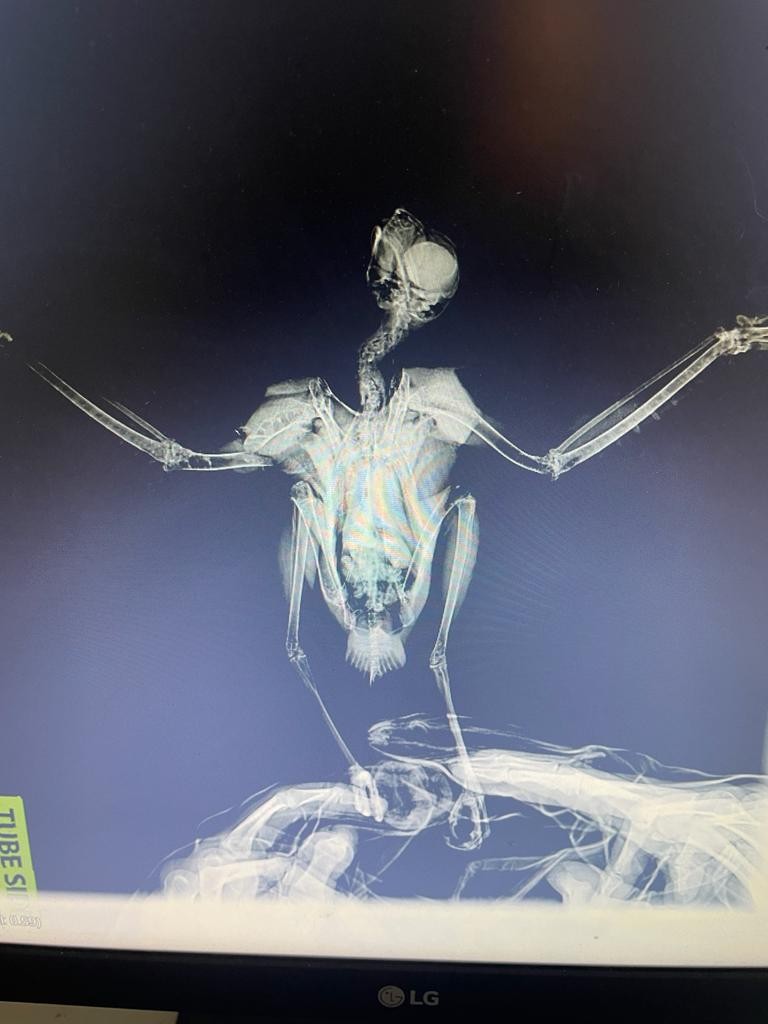

Şahin yavrusunu kurtarmak için seferber oldu

BODRUM’DA EVİNİN CAMINA CARPAN ŞAHİN YAVRUSUNU GÖREN EV SAHİBİ ŞOK OLDU. BAŞAK BİR BÖLGEDE YETİŞKİN BİR ŞAHİN İSE YARALI OLARAK BULUNARAK TEDAVİ ALTINA ALINDI

Bodrum’da evinin camına çarpan şahin yavrusunu gören ev sahibi seferber olurken, başka bir bölgede de yetişkin bir şahin yaralı olarak bulunarak tedavi altına alındı.

Gölköy Mahallesi Atatürk Caddesi üzerindeki bir evin camına çarparak yaralanan yavru şahin gören ev sahipleri durumu Bodrum Belediyesi’ne bildirdi. İhbar üzerine eve gelen Bodrum Belediyesi Torba Sokak Hayvanları Geçici Bakımevi ve Rehabilitasyon Merkezi’ne bağlı Petbulance ekibi, şahine ilk müdahalesini olay yerinde yaptı. Ekip daha sonra şahin yavrusunu merkeze naklederek tedavi altına aldı. Paraziter toksikasyon şüphesiyle tedavi altına alınan şahin yavrusunun hayati tehlikesinin olmadığı ve gözlem altında tutulduğu bildirildi.

Yetişkin şahin de tedavi altında

Gümüşlük Mahallesi’nde bir evin bahçesinde de kanadı kırık olarak bulunan yetişkin şahin duyarlı vatandaşların ihbarı ile belediye ekipleri tarafından alınarak tedavi edilmek üzere Torba Sokak Hayvanları Geçici Bakımevi ve Rehabilitasyon Merkezi’ne sevk edildi. Veteriner Hizmetleri Müdürlüğü yetkilileri, yaban hayvanlarının tedavisi tamamlandıktan sonra Doğa Koruma ve Milli Parklar Müdürlüğü ekiplerine teslim edileceğini açıkladı.